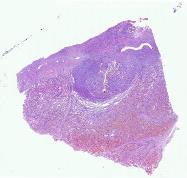

10532 |

胸腺 |

女, 36岁, 近4个月来间断发热,就诊于当地医院,胸部CT示前纵隔血管前间... |

上海市第一人民医院 |

有诊断 |